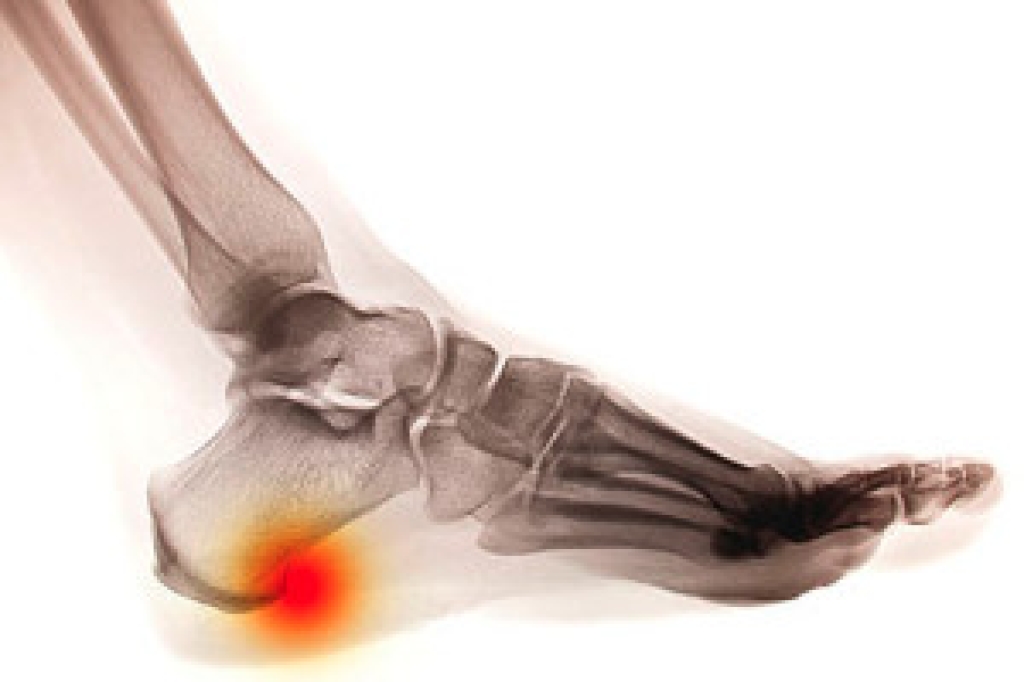

- Loss of circulation in legs & feet

Diabetes and poor circulation can cause general loss of sensitivity over the years, turning a simple cut into a serious issue.